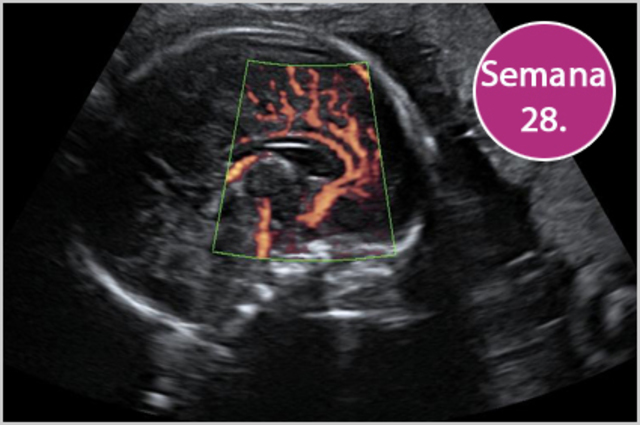

• Semana 28

Semana 28

28ª semana (7º mes): el feto pesa entre 1000 gramos y 1300 gramos. Las arrugas de la piel comienzan a desaparecer porque se deposita tejido graso debajo de la dermis. El cabello es más largo que los pelos del resto del cuerpo. Los bordes de los párpados, que estaban unidos desde el tercer mes, se separan. Los pulmones comienzan a adquirir movimientos respiratorios. El sistema nervioso central puede regular la temperatura y los movimientos respiratorios.